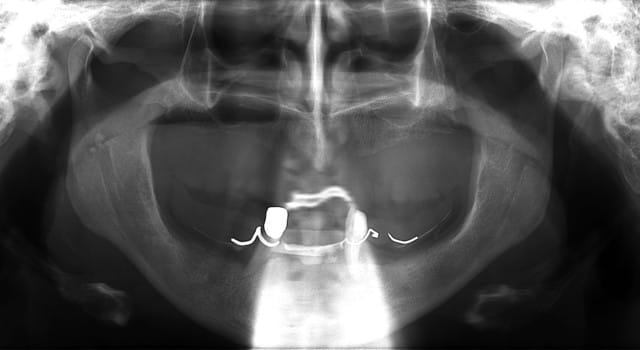

des photos ?

ok , en voilà...

ceux sont les photos du guide radio.

Mon prothésiste est un petit rigolo qui s'amuse à colorer les dents.

Ici le guide radio est préparé pour laisser passer l'embout de calage lors de la tomosynthèse de façon à ce que les deux appareils soient parfaitement stables.

les deux incisives centrales sont donc meulées.